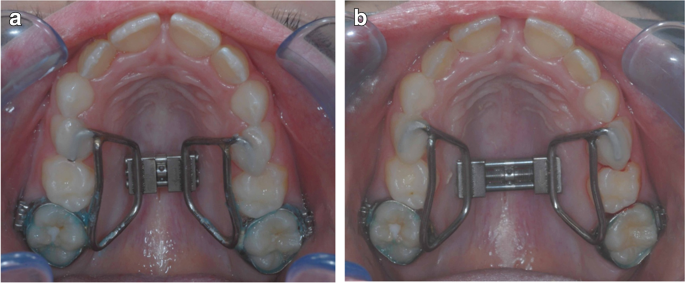

Os dispositivos mais utilizados incluem expansores do tipo Hyrax, Haas e suas variações contemporâneas, além de aparelhos assistidos por mini-implantes.

Após a instalação, inicia-se a fase de ativação do parafuso expansor.

O protocolo clássico envolve ativações diárias ou semi-diárias, conforme o planejamento individualizado.

Cada ativação promove um afastamento progressivo das hemi-maxilas.

Clinicamente, observa-se o surgimento de um diastema interincisal, considerado um sinal clássico de disjunção sutural efetiva.